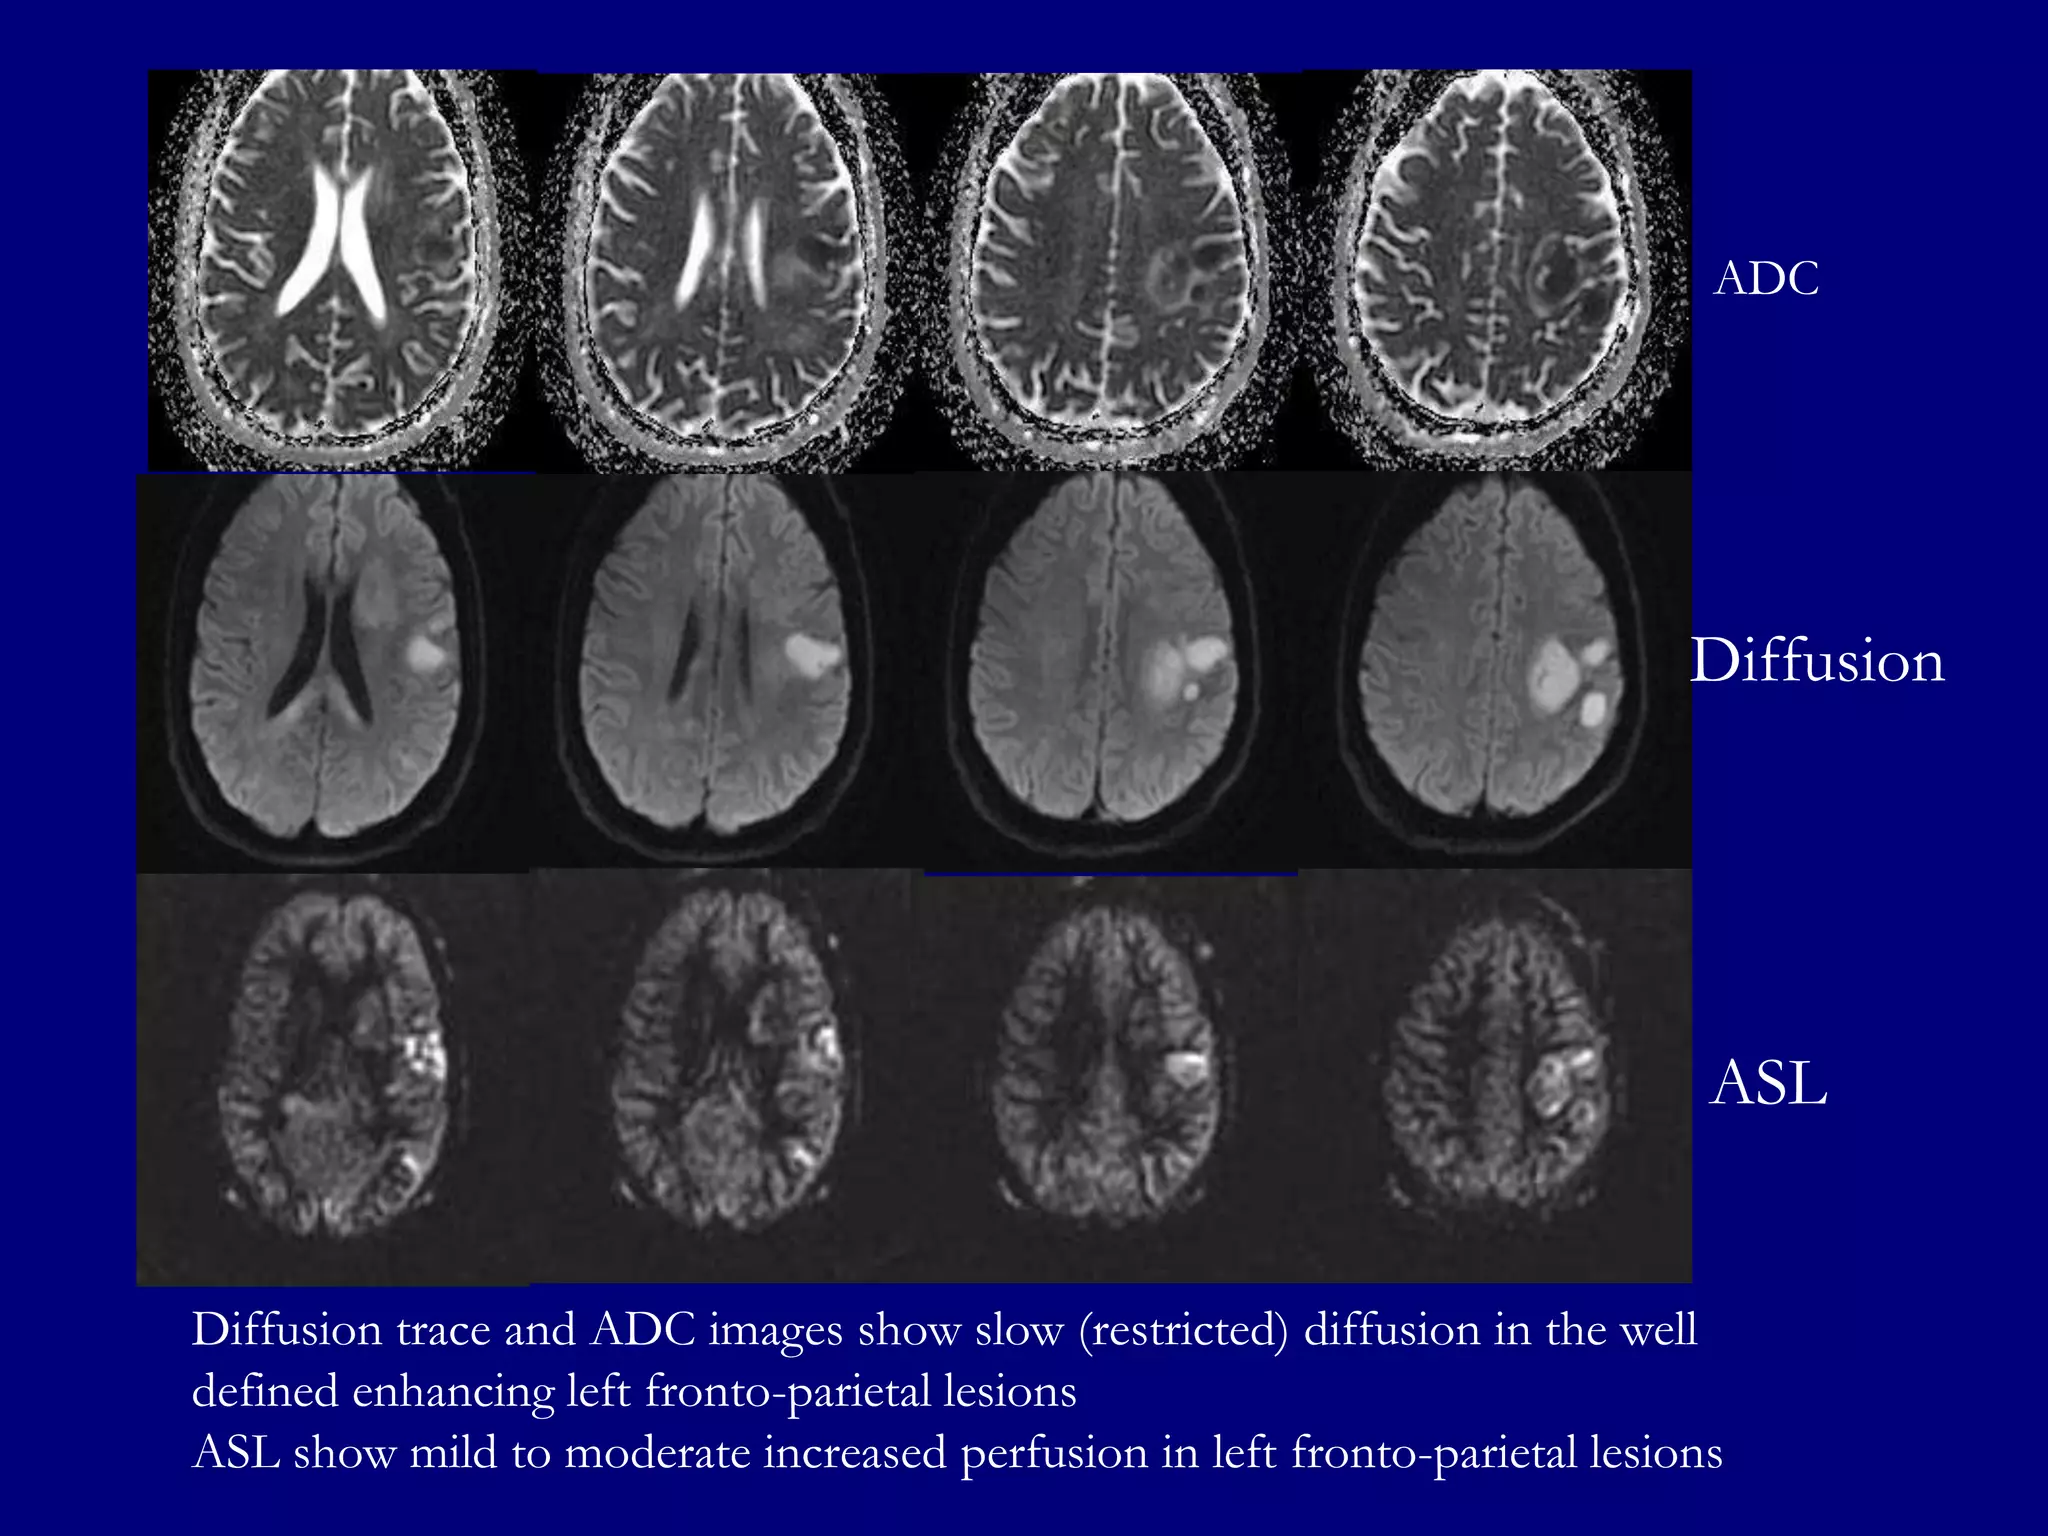

ADC

Diffusion

ASL

Diffusion trace and ADC images show slow (restricted) diffusion in the well

defined enhancing left fronto-parietal lesions

ASL show mild to moderate increased perfusion in left fronto-parietal lesions